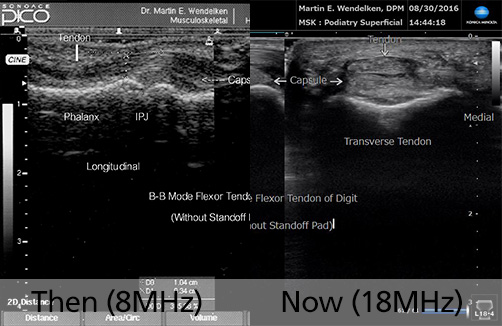

Then (2007) & Now (2020)

8MHz vs 18MHz

• Image 5: Flexor Tendon of Digit